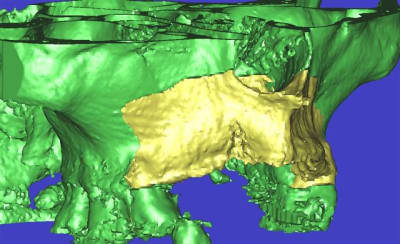

l'étude en partant des blocs standards

La première diapo est un essai pour justifier le concept (os non destiné à une utilisation greffe)

la deuxième est "tapée" dans une tête de femur de mauvais qualité (rejetée)

la troisième et suivante ce sont "les greffons" définitifs.

concept très prometteur. on obtient effectivement un contact intime du greffon avec le site receveur.